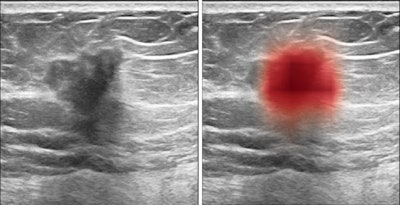

An artificial intelligence (AI) algorithm was able to significantly reduce false positives in breast ultrasound, potentially avoiding the need for one out of four biopsies in a study published online September 24 in Nature Communications.

Researchers from New York University (NYU) trained a deep-learning algorithm on nearly 290,000 breast ultrasound images. In the retrospective reader study, the model helped radiologists decrease false-positive rates by more than 37% and biopsy requests by more than 27% -- without affecting sensitivity. In addition, the algorithm demonstrated excellent generalizability on an external set of test data.

Although ultrasound offers value for detecting mammographically occult breast cancers -- especially in dense breasts -- the modality is also characterized by a high false-positive rate, according to the researchers. NYU co-first investigators Yiqiu "Artie" Shen, Farah Shamout, PhD, and Jamie Oliver and colleagues sought to address this problem by developing an AI algorithm.